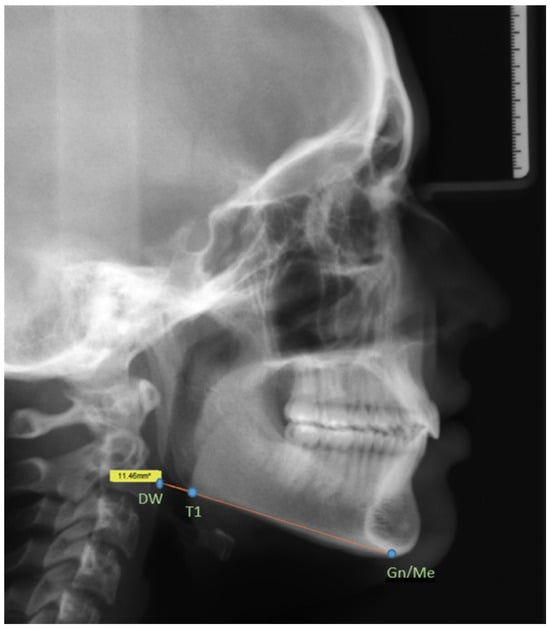

For digital lateral cephalograms, two lateral cephalograms were taken during treatment: one before the MARA and multibracket insert (T1) and one after the removal of all orthodontic appliances (T2). All lateral cephalograms were taken using the ORTHOPHOS XGPlus DS/Ceph X-ray machine (formerly, Sirona Dental Systems, Bensheim; presently, Dentsply Sirona Deutschland GmbH, Bensheim, Germany). Digital acquisition, storage and tracing as well as PAS measurements were performed with the software Sidexis XG version 2.56 (formerly, Sirona Dental Systems, Bensheim, Germany; presently, Dentsply Sirona Deutschland GmbH, Bensheim, Germany). To measure changes in the lumen, we selected three remarkable and reproducible markers (see Figure 1). The parameters used in this study were based on the parameters from Kinzinger et al. [20]. The authors selected parameters at the P4 level, focusing on the “mandibular PAS” according to Barrera et al. [21]. Measurements were performed by two clinicians: NP and ZS.

Figure 1. Lateral cephalogram with indicated reference point: Gn/Me (gnathion/menton), T1 (tangent point 1) and DW (dorsal wall). T1 tangent point 1: the intersection of a tangent through Gn with the caudal demarcation of the corpus mandibulae near the gonial angle, which is the Me/Gn (the menton or gnathion following the use of the Hasund index) and the caudalmost point of the mandibular symphysis in the mediosagittal plane. The American definition of the T1 tangent point is the “menton” and the DW (dorsal wall): the intersection of the mandibular plane with the dorsal wall of the PAS.